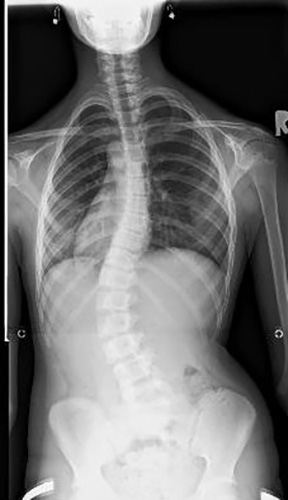

לפני ואחרי טיפול בעקמת 1

אחרי 3 חודשי טיפול מאחור לפני טיפול - מאחור